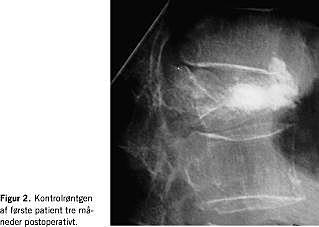

I. En 75-årig kvinde blev indlagt efter et mindre faldtraume i hjemmet. Ved en røntgenundersøgelse af columna sås en kompressionsfraktur i corpus af 12. torakalhvirvel (Figur 1 ). Trods analgetikabehandling var det ikke muligt at mobilisere patienten, da hun havde mange smerter. Efter samråd med patienten udførtes en perkutan transpedikulær vertebroplastik.